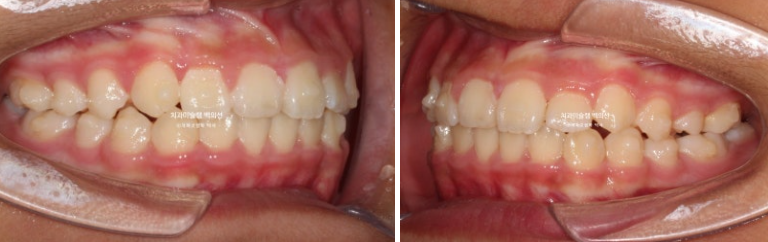

악궁확장을 통한 덧니배열을 목표로 인비절라인퍼스트 교정치료 권유드렸습니다.

24년 2월부터 9월까지, 첫세트의 19

개 장치를 모두 낀 후 모습입니다.

24.09

중심선은 개선되었으나 약간의 불일치가 남아있으며 반대교합과 덧니는 모두 개선되었습니다.

그 사이 하나 남아있던 유치가 빠지고 완전한 영구치열에 접어들었습니다.